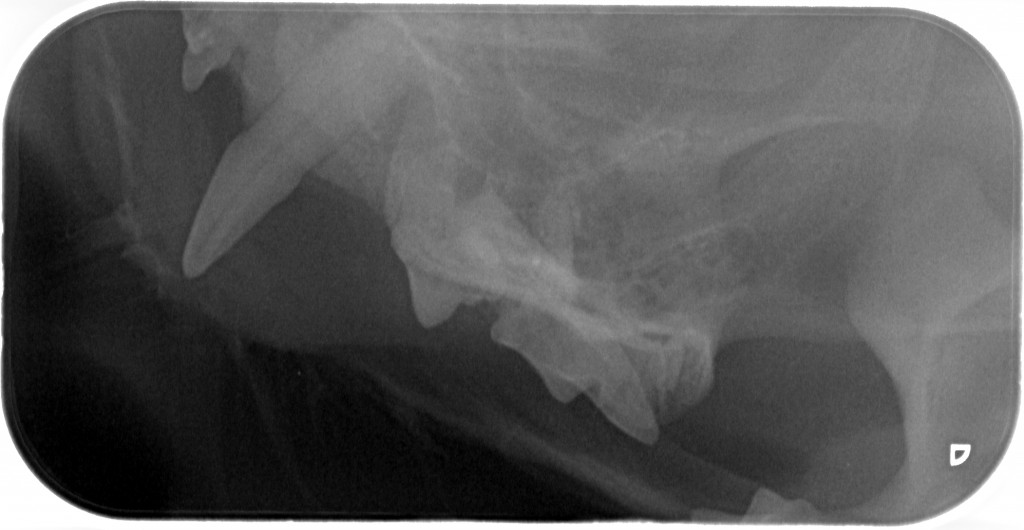

www.kattensliv.dk_Sygdomme hos katte fra P-T_Tænder_Mundproblemer_Shana-Mio_7

Fuld størrelse er

1024 × 530